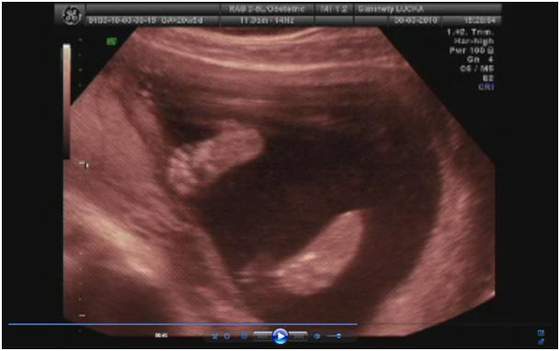

a lekarz na to "bardzo serdecznie zapraszam"

no niby 3500 ale to raczej mało możliwe (sam przyznał) skoro 2 tygodnie temu miała 2700

ale usg było jakie było i kazał się tym nie sugerować -ważne że urosła